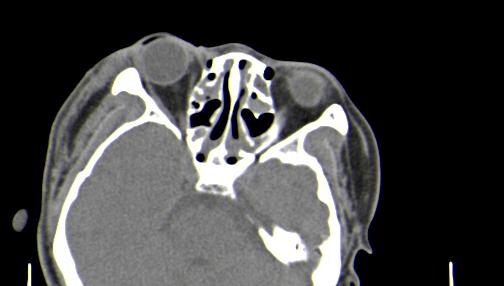

以下是引用皎皎白驹在2006-11-29 8:48:00的发言:[br]影像表现:双侧筛窦和上颌窦、鼻腔内均密度增高,右侧视神经增粗、弯曲,左筛窦顶部筛板及右侧纸板近视神经孔区可见骨折线。[br]结合临床表现考虑:右侧筛窦纸板近视神经孔区骨折致右侧视神经损伤。最好做个眼眶冠状扫描,更明确右侧视神经管是否狭窄。

以下是引用w_jianhua在2006-11-29 10:07:00的发言:[br]影像表现:双侧筛窦和上颌窦、鼻腔内均密度增高,右侧视神经增粗、弯曲,左筛窦顶部筛板及右侧纸板近视神经孔区可见骨折线。[br]结合临床表现考虑:右侧筛窦纸板近视神经孔区骨折致右侧视神经损伤。最好做个眼眶冠状扫描,更明确右侧视神经管是否狭窄。 [br] [br]支持[br]

以下是引用守望可可西里在2006-11-29 9:46:00的发言:[br][quote]以下是引用皎皎白驹在2006-11-29 8:48:00的发言:[br]影像表现:双侧筛窦和上颌窦、鼻腔内均密度增高,右侧视神经增粗、弯曲,左筛窦顶部筛板及右侧纸板近视神经孔区可见骨折线。[br]结合临床表现考虑:右侧筛窦纸板近视神经孔区骨折致右侧视神经损伤。最好做个眼眶冠状扫描,更明确右侧视神经管是否狭窄。